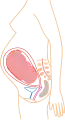

De acuerdo a su desarrollo, el embarazo se suele dividir en tres etapas de tres meses cada una, con el objetivo de simplificar la referencia a los diferentes estados de desarrollo del feto.

El tercer trimestre marca el principio de la viabilidad —aproximadamente después de la semana 25— que quiere decir que el feto podría llegar a sobrevivir de ocurrir un parto prematuro, parto normal o cesárea. Ya que a partir de este momento los pulmones fetales se encuentran formados casi totalmente, solo les falta madurar.

Mes 5: Mide 18 cm y pesa 500 g. Crece el cabello de la cabeza, pestañas y cejas. Desarrollo del sistema inmunitario Mes 6: Mide 25 cm y pesa 1000 g. La cara ya está completamente formada. La piel se cubre de un material graso llamado vérnix caseoso. Abre los ojos y se mueve mucho.

Mes 6: Mide 25 cm y pesa 1000 g. La cara ya está completamente formada. La piel se cubre de un material graso llamado vérnix caseoso. Abre los ojos y se mueve mucho. Mes 7: Mide 30 cm y pesa 1500 g. Comienzan a moverse los pulmones. Aumenta la grasa subcutánea y ya no cabe bien en el útero.

Mes 7: Mide 30 cm y pesa 1500 g. Comienzan a moverse los pulmones. Aumenta la grasa subcutánea y ya no cabe bien en el útero. Mes 8: Mide 35 cm y pesa 2500 g. Generalmente se pone boca abajo (posición cefálica) Se engrosa la piel, adquiriendo el tono rosáceo que tendrá definitivamente.